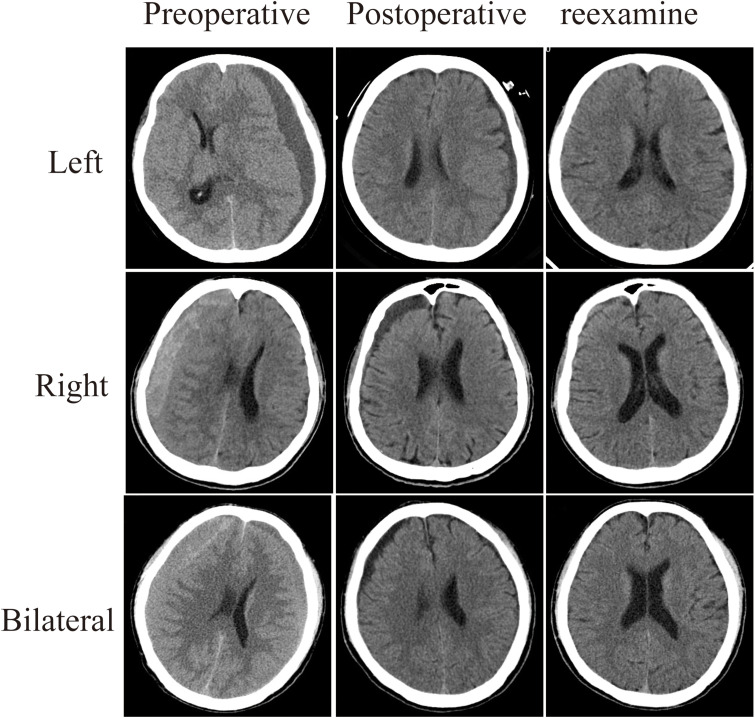

Abstract Image